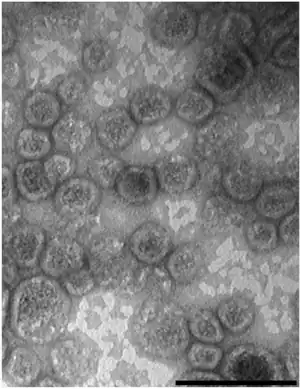

| Gram negative Shigella sonnei bacteria which spent 48 hours cultured on Hektoen enteric agar (HEK). | |

Shigella sonnei is a species of Shigella.[2] Together with Shigella flexneri, it is responsible for 90% of shigellosis cases.[3] Shigella sonnei is named for the Danish bacteriologist Carl Olaf Sonne.[4][5] It is a Gram-negative, rod-shaped, nonmotile, non-spore-forming bacterium.[6]